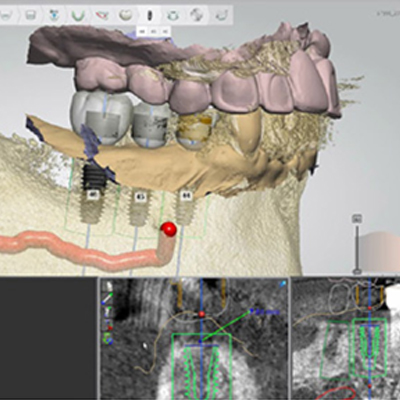

임플란트 수술 전 3D CT를 분석하여 모의 수술하게 되며,

골조직과 신경의 위치를 정확하게 파악하고 시뮬레이션 함으로써

신경손상 가능성이 전무하며 미리 계획된 방향과 위치에 임플란트를 식립할 수 있습니다.

오차 없는 식립을 위해 구강용 정밀 3D 프린터를 이용하여 개인 맞춤형 수술 가이드를 제작합니다.

가이드 수술을 이용한 임플란트 수술은 계획된 위치에 임플란를 식립할 수 있어

간단하고 안전한 수술이 가능합니다.

또한 잇몸 절개 없이 임플란트가 들어갈 수 있는 크기로만 작은 구멍을 내어 수술하므로 통증이 적고 빠른 회복이 가능합니다.